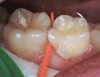

Fig 4. Three thin soft dental picks were used simultaneously for SDF proximal surface saturations in a teenaged patient (Fig 3). After 60 seconds, the treated regions were covered with 5% fluoride varnish (Fig 4). A comparison can be seen of pre-SDF-treatment bitewing films (Fig 5) and 8-month post-SDF bitewing films (Fig 6) for the patient shown in Fig 3 and Fig 4. Radiolucencies were similar or improved, except for contact of maxillary first and second molars.

Fig 3. Three thin soft dental picks were used simultaneously for SDF proximal surface saturations in a teenaged patient (Fig 3). After 60 seconds, the treated regions were covered with 5% fluoride varnish (Fig 4). A comparison can be seen of pre-SDF-treatment bitewing films (Fig 5) and 8-month post-SDF bitewing films (Fig 6) for the patient shown in Fig 3 and Fig 4. Radiolucencies were similar or improved, except for contact of maxillary first and second molars.

Interproximal insertion of SDF is demonstrated in different patients in Figure 3 through Figure 11. Various diameters and brands of soft dental picks may be used depending on the closeness of the proximal surfaces and ease of insertion; for example, some picks are designed for use in wider spaces between teeth. This protocol also offers versatility. Figure 3, for example, shows the simultaneous use of three thin soft dental picks to saturate proximal surfaces with SDF in a teenaged patient; the treated regions were subsequently covered with fluoride varnish (Figure 4). This patient was initially treated in April 2019 (Figure 5), with an identical re-application 3 months later. As shown in Figure 6, the December 2019 bitewing film revealed good results with the possible exception of the contact regions of the maxillary first and second molars. New SDF application was completed in the December appointment.

The authors' protocol for insertion of SDF-coated soft dental picks involves isolating the teeth with cotton rolls or other means, flossing the interproximal site to clear food debris and dental plaque, and then inserting a SDF-coated pick (Figure 1 and Figure 2) to saturate the contacting surfaces of the teeth with the fluid. This treatment is painless and requires no anesthetic. The pick should remain in place for at least 60 seconds and can be gently pulled in and out to agitate the fluid for enhanced surface coverage by capillary action. Additional SDF can be wiped on, using a small applicator, above the contact and in the buccal and lingual sluiceways. Excess fluid and any blood elicited may be blotted with a cotton swab. An additional 60-second insertion may be applied in the same way if there is radiographic evidence of a deeper decalcification or caries lesion. With the pick still in place, 5% (or 2.5%) fluoride varnish is painted over the treatment area, and the pick is then withdrawn.